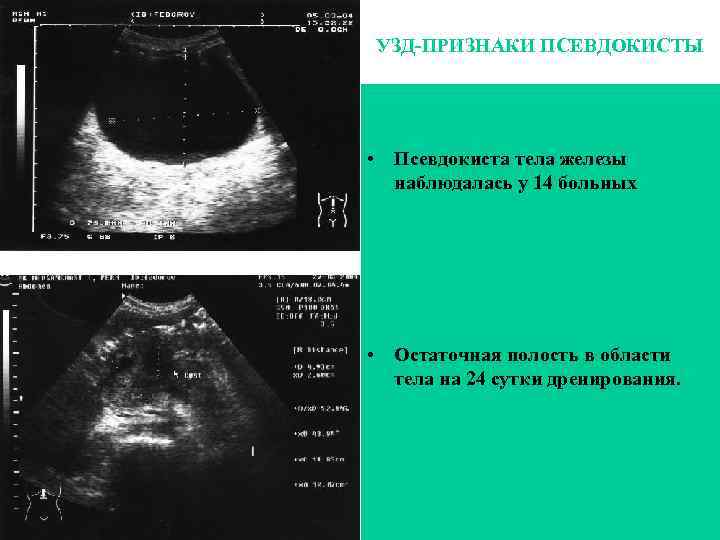

УЗД-ПРИЗНАКИ ПСЕВДОКИСТЫ • Псевдокиста тела железы наблюдалась у 14 больных • Остаточная полость в области тела на 24 сутки дренирования.